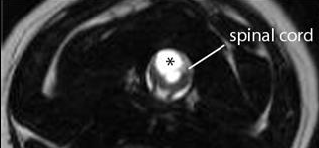

FIGURE

2: T2 weighted transverse image through a wide syrinx (asterisks)

demonstrating the asymmetrical involvement of the right spinal cord dorsalhorn.

The most important and consistent clinical sign of CM/SM is pain however this may be difficult to localise. Owners may describe postural pain; for example, affected dogs may suddenly scream and/or lie with the head on the ground between the paws after jumping up or during excitement. It is also common to sleep with the head in unusual positions, for example elevated. Discomfort often appears worse in the evening and early morning or when excited and can be associated with defecation or may vary with weather conditions. Pain is positively correlated with syrinx width and symmetry (Fig 2); i.e. dogs with a wider asymmetrical syrinx are more likely to experience discomfort, and dogs with a narrow syrinx may be asymptomatic, especially if the syrinx is symmetrical. Dogs with a wide syrinx may also scratch, typically on one side only, while the dog is walking and often without making skin contact, such behaviour is often referred to as an “air guitar” or “phantom” scratching. Dogs with a wide syrinx are also more likely to have scoliosis. In many cases the scoliosis slowly resolves despite persistence of the syrinx.